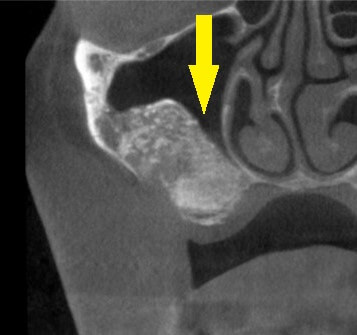

インプラントを埋入するには骨が薄いため、抜歯後、まずはサイナスリフトという骨造成を行い、十分な骨量を確保して、本日インプラント埋入術を行いました。

下の写真上段が術前のレントゲン写真、2段目が術前のCT、3段目がサイナスリフト後、4段目がインプラント埋入後のCTです。